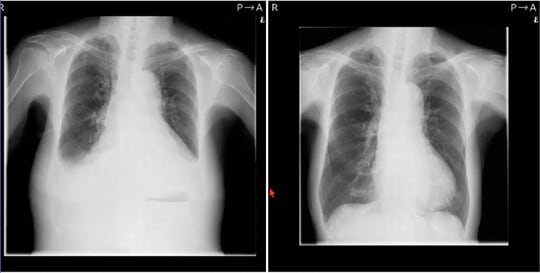

今回紹介するのは、92歳の女性患者Dさんの事例です。まずは、下記のレントゲン写真を見てください。

左側が筆者のクリニックに入院したばかりのころ、右側がカテーテルアブレーション治療をし、1年ほど経過したころです。左側のレントゲン写真を見て、筆者は「早ければ数日、長く見積もってもあと1ヵ月の命」と診察しました。